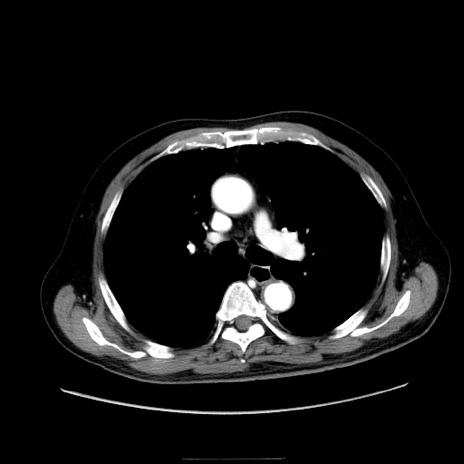

冠状断像

【症例】80歳代男性

【現病歴】約6時間前から臍下部痛が出現。次第に腹部膨隆・背部痛も生じてきたため来院。背部痛の場所は変化しない。

【身体所見】意識清明、BT 36.3℃、BP  131/87mmHg、P 87bpm、SpO2 100%(RA)、臍周囲自発痛・圧痛あり、反跳痛なし、自発痛部位に一致して板状硬あり、腹部膨隆、腸雑音減弱、CVA tenderness両側陰性。